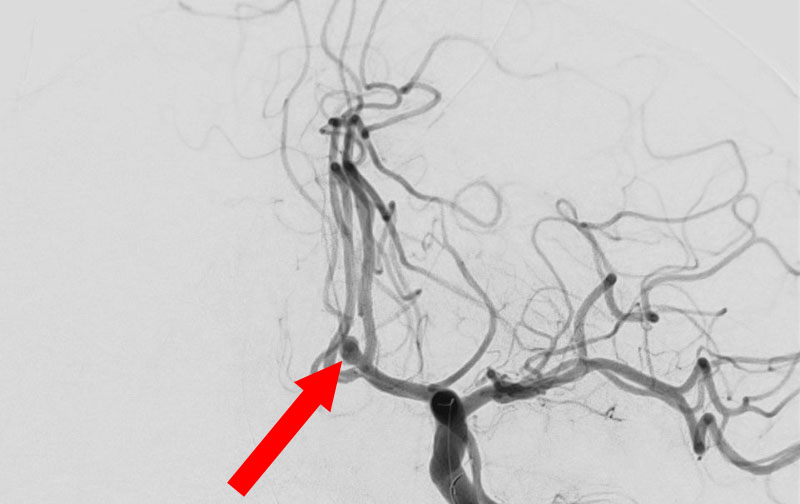

No.1628 手術前

No.1628 手術中

No.1628 手術後